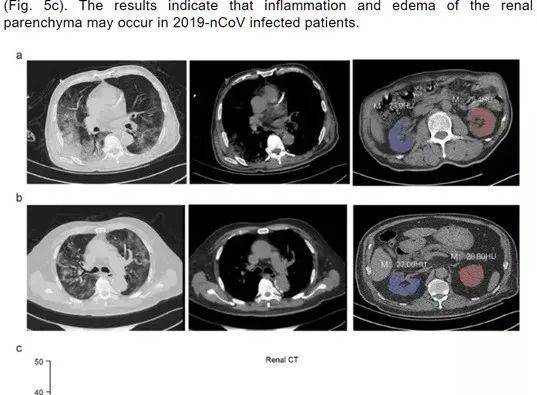

早在4月,就有研究指出,新冠患者普遍存在腎髒損害的情況。

一篇題爲Caution on Kidney Dysfunctions of 2019-nCoV Patients的論文在研究了59名來自武漢、黃石和重慶的59例感染患者病例後,發現63%的患者表現出腎功能不全的症狀,CT掃描顯示100%的患者腎髒影像學異常。

與此同時,英國和加拿大也發現,接受重症監護的新冠患者中,有8%-12%出現了肝或腎衰竭,需要靠長年透析治療才能生存。

中國醫學科學院基礎醫學研究所副所長黃波表示,感染者的肝腎受損可能是由于肺部功能障礙導致:

“呼吸功能出現障礙時,氧氣交換受阻,其它髒器會處于乏氧狀態,而對氧特別敏感的腎髒往往會發生嚴重的功能性損傷。”